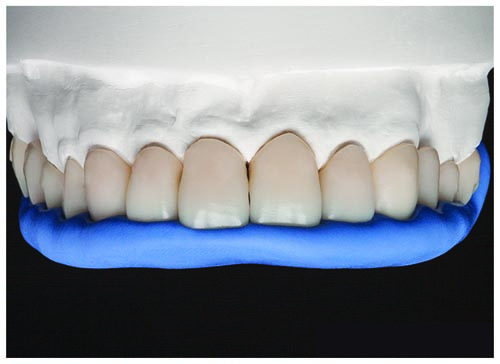

Fig. 12: It was very important to illustrate for the patient what the anticipated aesthetic and functional outcomes would look like, even before any procedures, to build his trust and confidence in the restorative process. Therefore, Smile Designer Pro was used to create a digital mock-up of the patient’s smile. This enabled the patient to visualize how his smile would be restored through a combination of root canal therapy, posts/cores and lithium disilicate crowns (e.g., IPS E.max) on teeth #6, #7, #8, #22 and #28; endosteal implants, custom abutments and IPS E.max crowns on teeth #3, #12 and #15; IPS E.max crowns on teeth #2, #4, #5, #10 (with post/core), #13 and #14; lithium disilicate (IPS E.max) veneers for teeth #9, #11 and #23 through #27; and conservative IPS E.max onlays for teeth #18 through #21 and #29 through #31. Alternative treatments discussed with the patient included a zirconia bridge spanning teeth #2 through #4, as well as for teeth #11 through #13. Regardless of the ultimate restorative decision, long-term provisionalization would be required for teeth #2 through #14.

Fig. 28: The completed Telio CAD provisional restorations were tried back onto the model to verify fit and aesthetic qualities.